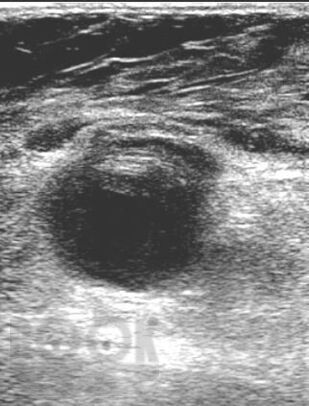

Учебное пособие содержит материал, отражающий представления об эпидемиологии, этиопатогенезе ятрогенных и инфицированных ложных аневризм магистральных артерий. Изложены современные методы клинико-лабораторной и инструментальной диагностики этой когорты пациентов. Освещены результаты хирургической тактики при лечении данной

патологии.